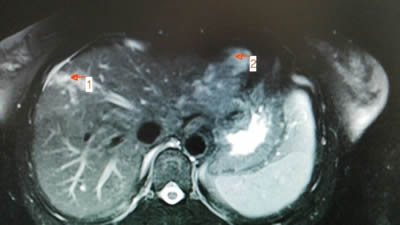

术中:DSA下肝左右叶血管瘤栓塞治疗后成像(见图标1、2) 半年后返院复查,肝左右叶血管瘤基本消失(见图标1、2)